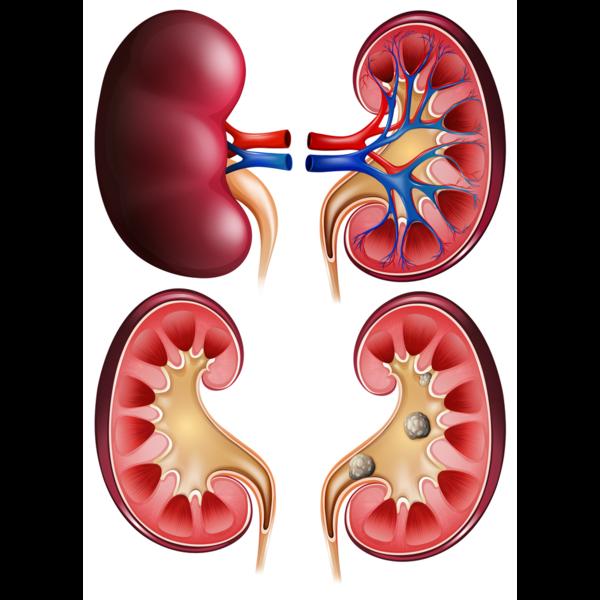

Best Kidney Stone Surgeon in Thane – Advanced Lase...

Kidney Stone Removal in Thane – Safe & Effective P...

Kidney Stone Removal Treatment in Siddharth Nagar,...

Top-Rated Kidney Stone Surgeon Near Me in Veer Sav...

Best Treatments for Kidney Stones at Our Clinic Ki...

Best Kidney Stone Treatment in Thane West – Non-Su...

Kidney Stone Pain in Thane – Advanced Treatment fo...

Exploring Advanced Urology Procedures in Thane Wes...